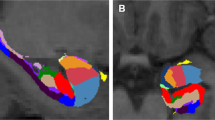

All anatomical images were acquired using the same Siemens Trio 3.0 Tesla MRI system (Trio, Siemens Medical Systems) scanner (3D, GRE (MPRAGE), axial, TR=1750 ms, T1=1100 ms, 25.6 cm FOV, 1.0 mm slice thickness, flip=20°, Bandwidth: (220 Hz/pixel), 256 (phase) × 256 (frequency), number of excitations=1). All T1 images were visually inspected to assure appropriate quality. Automated segmentation and labeling of the amygdala, hippocampus, ACC, and vmPFC, and estimation of total intracranial volume from participants’ T1 images were performed using the FreeSurfer image analysis suite (version 5.1.0; http://surfer.nmr.mgh.harvard.edu/) and its library tool recon-all. Details of these FreeSurfer parcellations were previously described (Fischl et al, 2004; Desikan et al, 2006; Destrieux et al, 2010). The use of FreeSurfer segmentation has been validated in youth as young as age 3, with results published in high-quality journals (Østby et al, 2009; Fjell et al, 2012). Automated segmentation of the amygdala and hippocampus compared with manual tracing with FreeSurfer was previously validated (Morey et al, 2009). Spatial normalization by affine registration to Talairach space and skull stripping were performed on the T1 images. FreeSurfer registration, segmentation, and labeling of structures were previously described (Morey et al, 2012). Registration and segmentation of the ROI were overlaid on original T1 images and visually inspected (CCH, RAM) slice-by-slice for correct location and shape. All scans were reviewed by a neuroradiologist who ruled out clinically significant abnormalities. Total vmPFC was composed of two regions defined by FreeSurfer terminology, the sum of the right and left medial orbitofrontal and lateral orbitofrontal cortexes (Desikan et al, 2006). This includes the ventral sector of the medial PFC, the orbitofrontal cortex medial to the straight gyrus, and the orbital sulcus laterally, and is consistent with other approaches (Boes et al, 2009). Total ACC volumes were summed from the following FreeSurfer parcellations: rostral and caudal ACC divisions; ACC sulcus and gyri; and subcallosal gyrus (Desikan et al, 2006; Destrieux et al, 2010) (Figure 1).

(a) Ventromedial prefrontal cortex (vmPFC) and anterior cingulate cortex (ACC) regions-of-interest as defined by FreeSurfer on a medial view of the right hemisphere (vmPFC in green and ACC in fuchsia). (b) This image of the vmPFC is from the ventral view in both hemispheres. The vmPFC, defined by FreeSurfer, is the sum of the right and left medial orbitofrontal and lateral orbitofrontal cortexes.